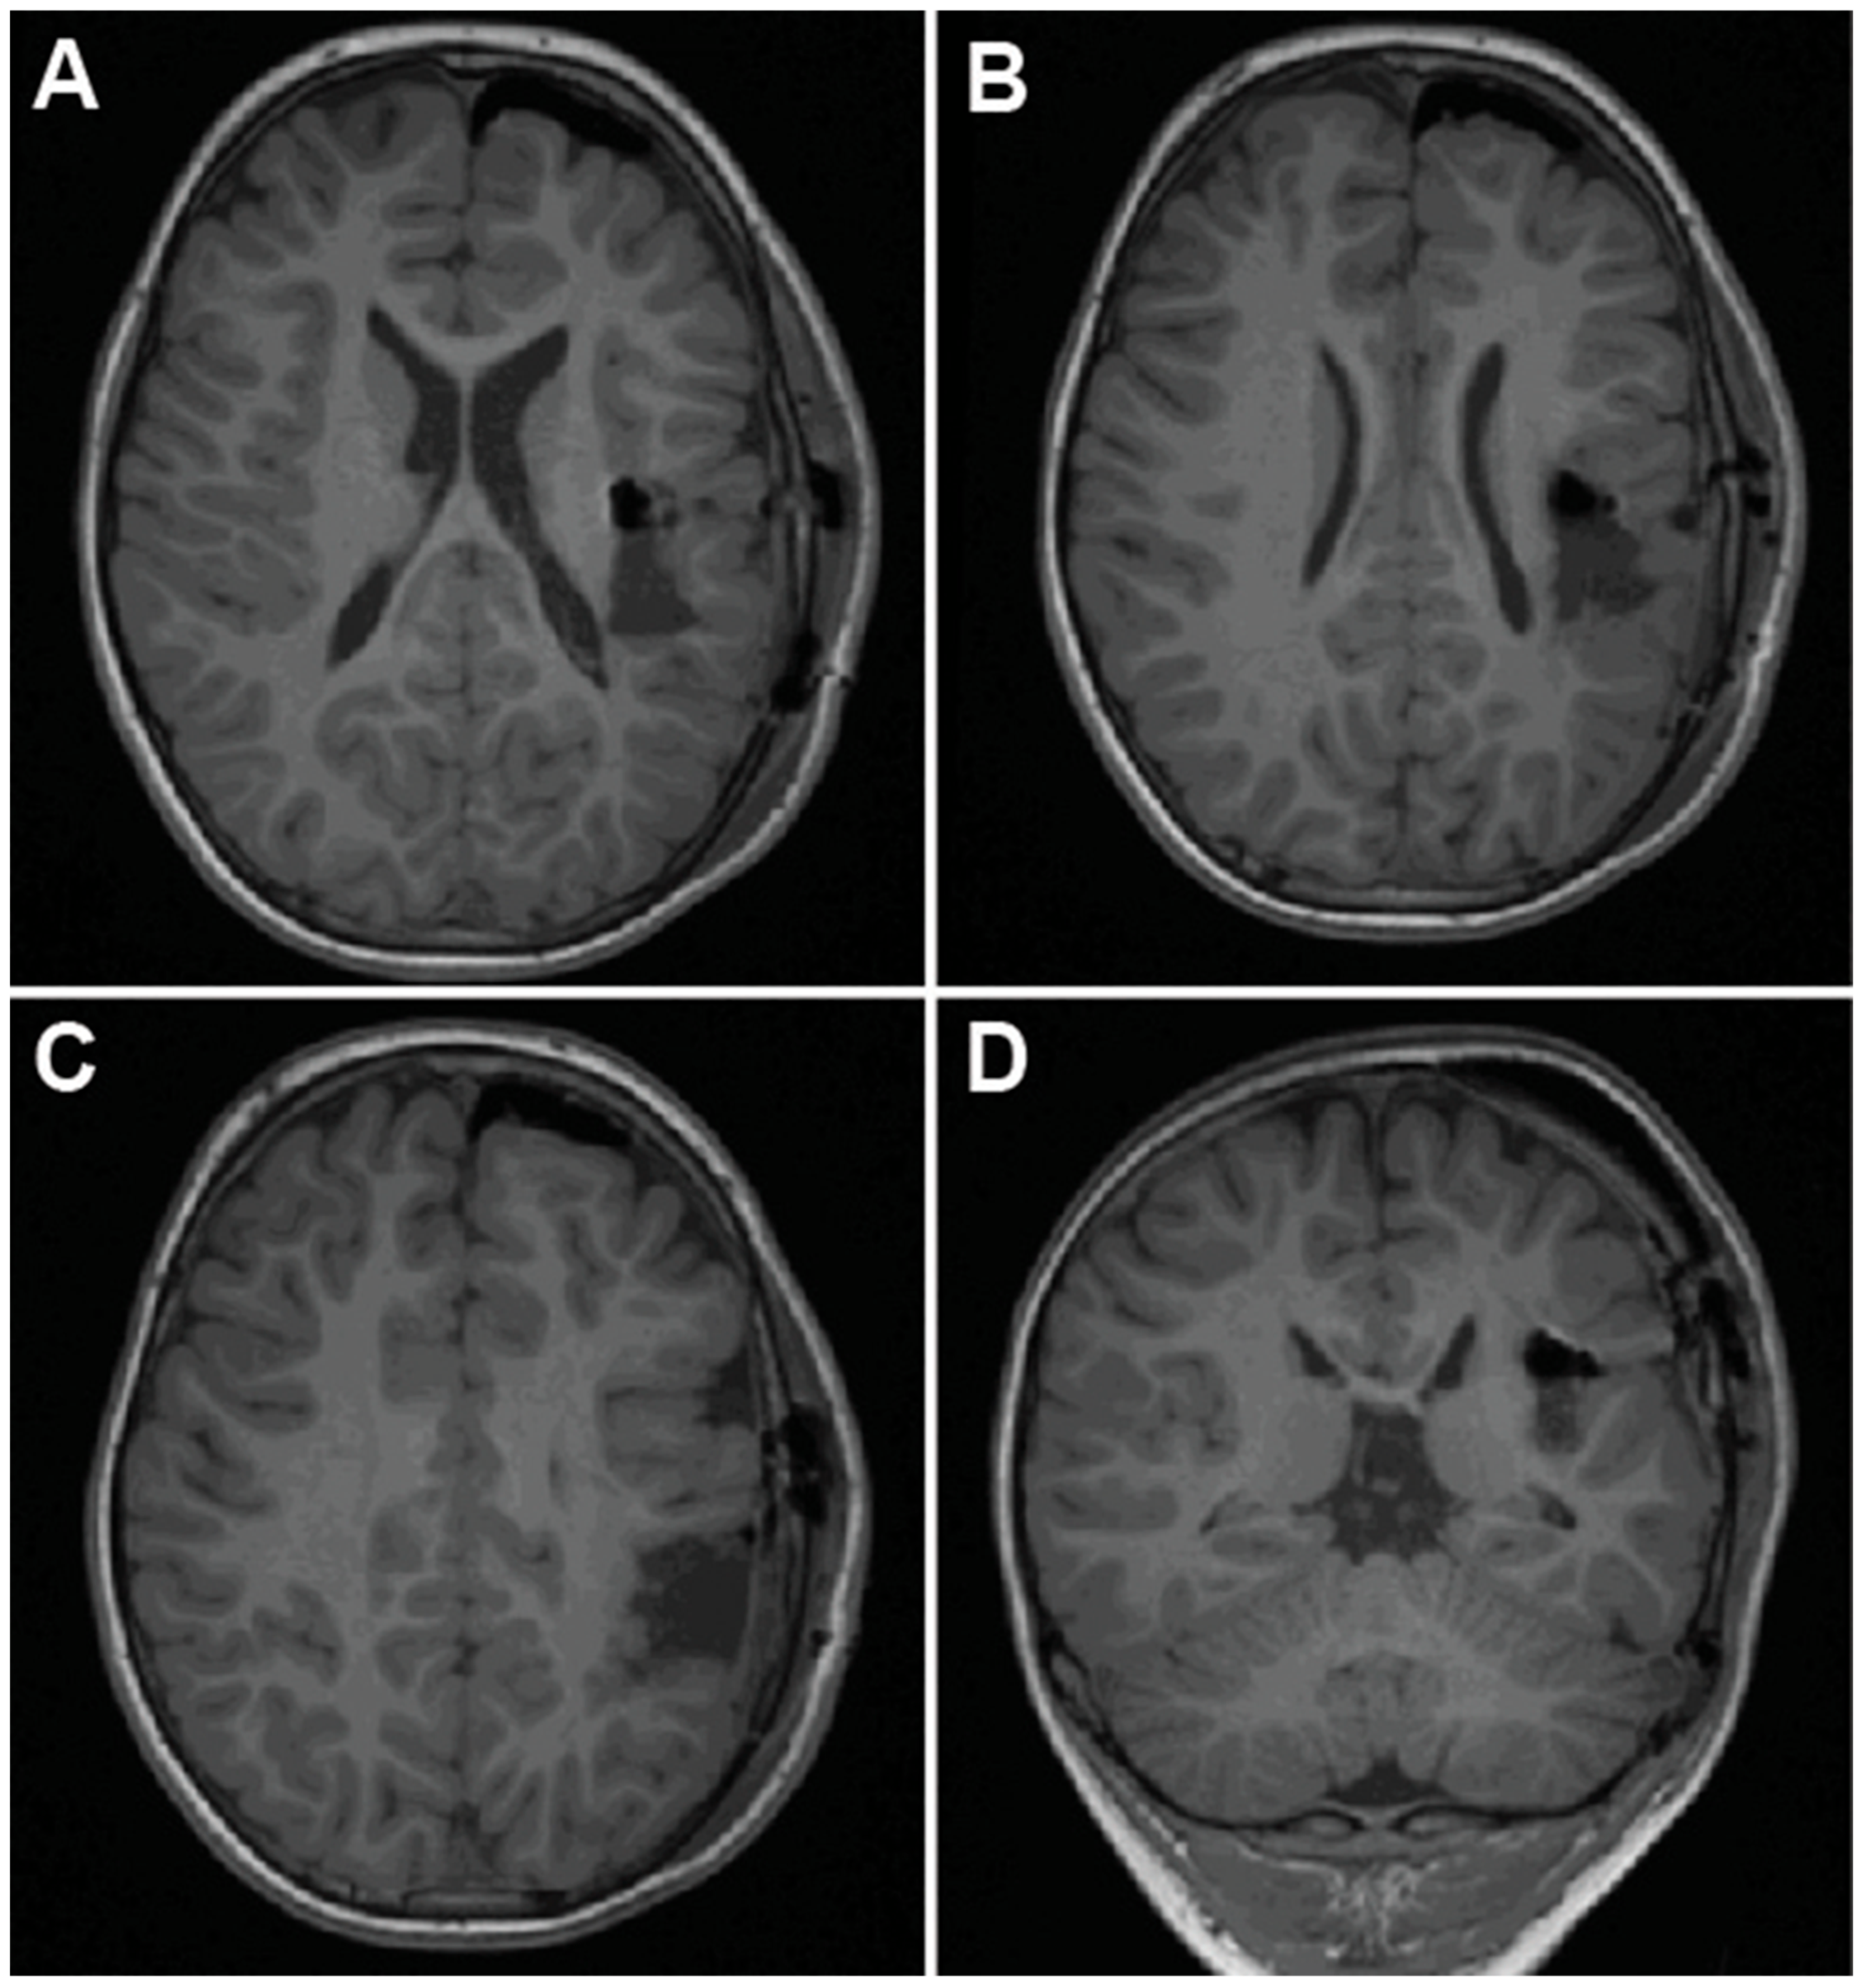

2.4. Case 4—Trans-Sylvian Approach for Idiopathic Insular Epilepsy